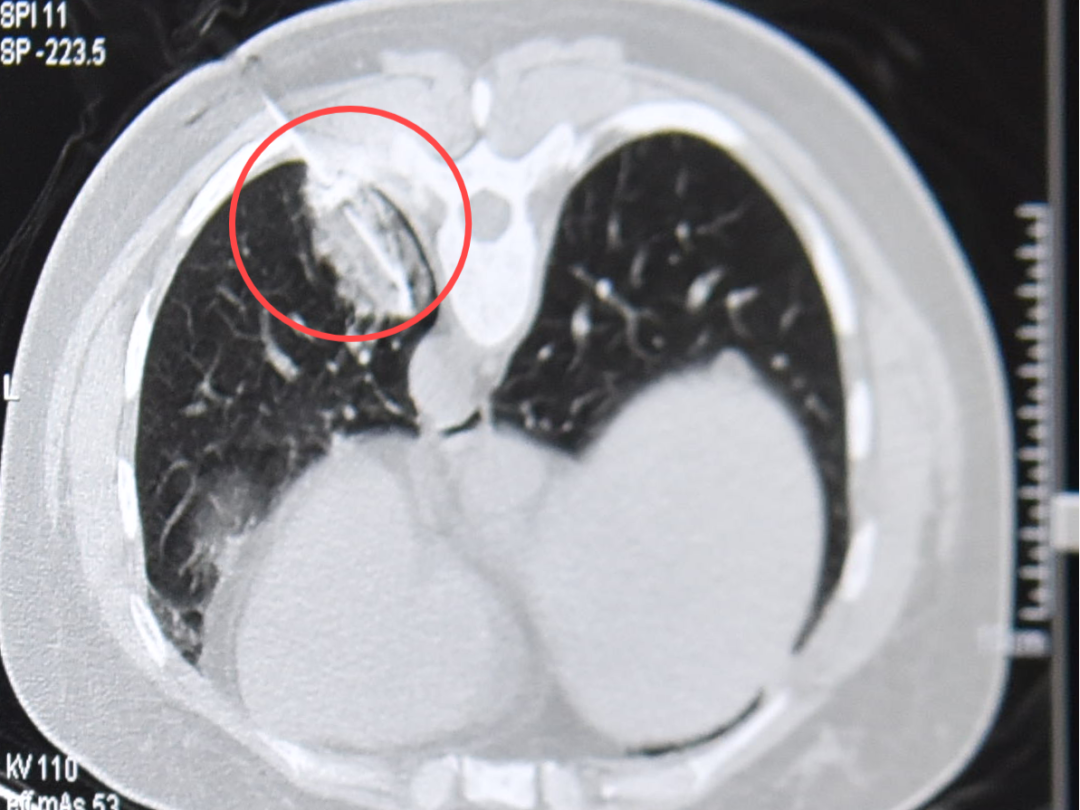

冷冻消融中

消融后,晕征范围完全覆盖结节位置